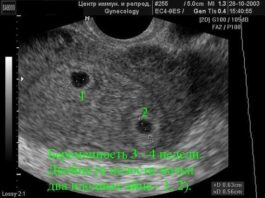

Отже, про УЗД. Сьогодні було планове УЗД, на якому був зроблений акцент на серце. Результат УЗД – все чудово, відхилень немає. Дівчина вела себе дуже спокійно, і настійно просила її не турбувати. Думаю, що дитина просто спав.